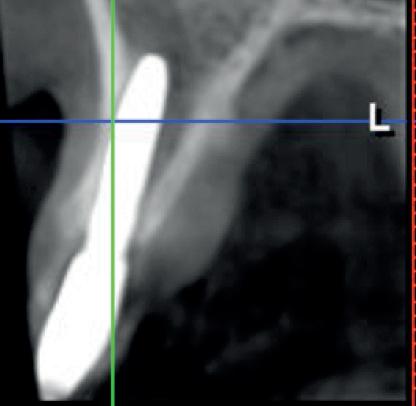

• Apprentissage et maîtrise de la lecture du scanner : planifications virtuelles.

• Anticiper la position clinique de l’implant à partir de sa position virtuelle.

L’objectif pédagogique réside également dans la volonté qu’aucun praticien ne se retrouve seul face à des patients présentant des plans de traitements simples ou complexes, seul aussi devant des interprétations

de scanners classiques ou délicates, ou seul encore pour effectuer des chirurgies courantes ou relevant de techniques avancées et ceci pendant et après le cursus.